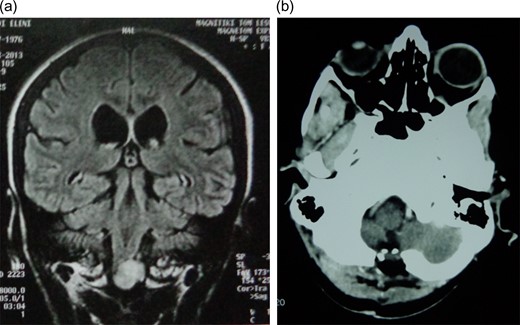

The second patient was a 36 years-old woman with medical history of chronic renal failure and secondary hypoparathyroidism. She had to undergo an MRI-scan of brain and cervical region to exclude ectopic parathyroid function. Her examination revealed incidentally a SOL that was high intensity on T1-sequences with dimensions of 1.1 × 1 cm at the level of the FM (Fig. 2a). She reported intermittent numbness of her upper extremities for the two last months. Again, gross total tumor resection was performed via a midline suboccipital craniectomy and C1 laminectomy (Fig. 2b). Intraoperative neurophysiologic monitoring was uneventful. The patient presented no postoperative complications and was discharged neurologically intact.

a) Coronal plane of preoperative MRI scan depicting a highly intense of foramen magnum of second patient. (b) Postoperative computer tomography (CT) scan showing total tumor resection.